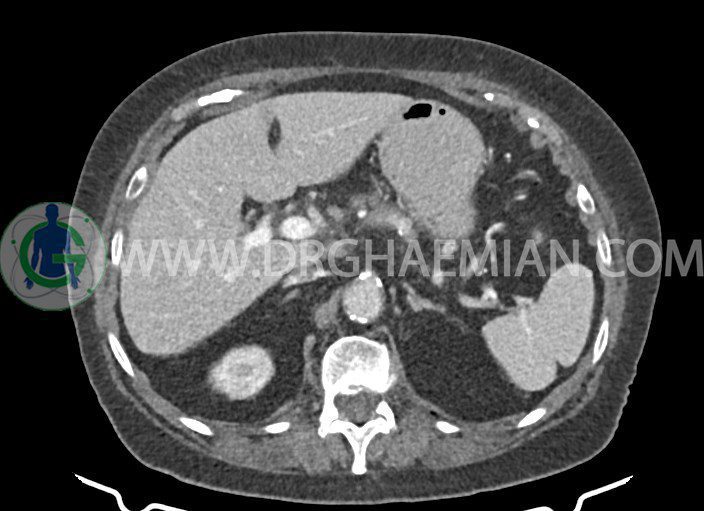

سی تی اسکن شکم و لگن با استفاده از اشعات ایکس تصاویر عرضی از ناحیه شکمی ایجاد میکند. در این کیس التهاب پانکراس، کیست کاذب پانکراس، کیست های کورتیکال، کلسیفیکاسیون دیواره آئورت و … مشاهده می شود.

در سي تي اسکن اسپيرال شکم و لگن بدون کنتراست و با کنتراست در فاز ارتريال و پورتوونوس (مولتي ديدکتور 16 با مقاطع ظريف و بازسازي هاي ساژيتال و کرونال):

– ساختمان سيستيک به ابعاد mm 25 x 35 در ناحيه سر و گردن پانکراس همراه با تجمع مقداري مايع در اطراف گردن و تنه پانکراس، بدون ديلاتاسيون مجراي پانکراس، مطرح کننده پانکراتيت و کيست کاذب پانکراس

– وجود مقداري اسلاژ در کيسه صفرا بدون نشانه هاي کوله سيستيت

– گرانولوم کلسيفيه بدون اهميت به قطر 7 mm در ساب کپسولر فوقاني سگمان 4 کبد

– کيست هاي کورتيکال 6 mm و 22 mm در کليه چپ و 7 mm 8,mm و 23 mm در کليه راست

– کلسيفيکاسيون ديواره ائورت، شريان هاي ايلياک و پروگزيمال شريان هاي سلياک و رنال و